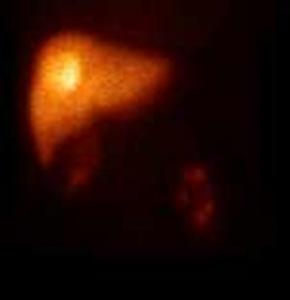

21.4.1.3.2. Somatostatin receptor scintigraphy

Many tumors express somatostatin receptors, especially the various types of neuroendocrine tumors (for example carcinoid, meningeoma, medulloblastoma and neuroblastoma). These can be investigated with somatostatin analogue peptides, most commonly with pentetreotide, an 111In isotope labeled peptide (OctreoScan). This examination is primarily significant in carcinoid and GEP (gastroenteropancreatic) tumor (gastrinoma, insulinoma, glucagonoma, VIPoma) diagnostics. Although GEP tumors present with a severe clinical picture, they are usually small and their detection with other imaging modalities is difficult. For this reason, somatostatin receptor scintigraphy is the recommended method of first choice. If the carcinoid is well differentiated, it is able to detect the lesion and possible metastases. Furthermore, it is useful in therapy monitoring and in cases of planned liver transplantation to rule out extrahepatic metastases. (Figure 13.)

Image

a

b

c

13. Somatostatin receptor scintigraphy (Octreoscan). Planar anterior (a), transversal (b) and coronal (c) fusion SPECT-CT images. Multiplex liver metastases, the primary neuroendocrine tumor is in the head of the pancreas.